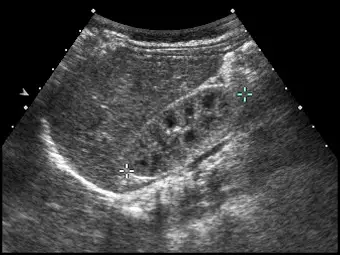

新生兒腎臟超音波掃描時,發現腎皮質回音強度明顯高於腎髓質(如下圖所示),最有可能的診斷為何?

- 影像整體特徵:為一張呈現腎臟縱切面(longitudinal view)的超音波掃描影像。

- 腎皮質(Renal cortex):影像中腎皮質的回音強度偏高(hyperechoic),亮度明顯較高,其回音程度通常與相鄰的肝臟或脾臟相當,甚至稍高。

- 腎髓質(Renal medulla):腎錐體(renal pyramids)呈現極為明顯的低回音(hypoechoic),外觀為多個排列整齊的三角形或橢圓形暗區。

- 皮髓質分界(Corticomedullary differentiation, CMD):由於皮質的高回音與髓質的低回音產生強烈對比,使得皮髓質的分界在影像上極為清晰。

- 其他發現:腎臟的集尿系統(collecting system)並無擴張,腎實質內未見異常囊腫(cysts),腎臟輪廓平順,可能有輕微正常的胎兒期小葉化(fetal lobulation)。